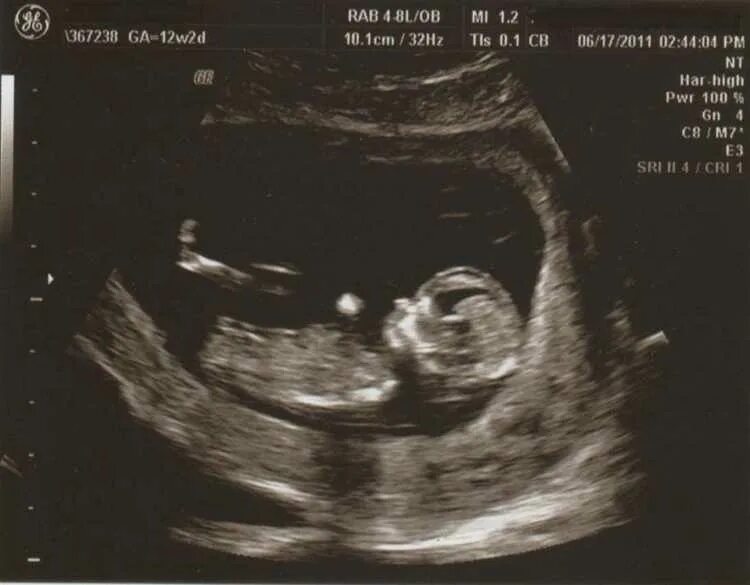

На каком сроке беременности чувствуется шевеление